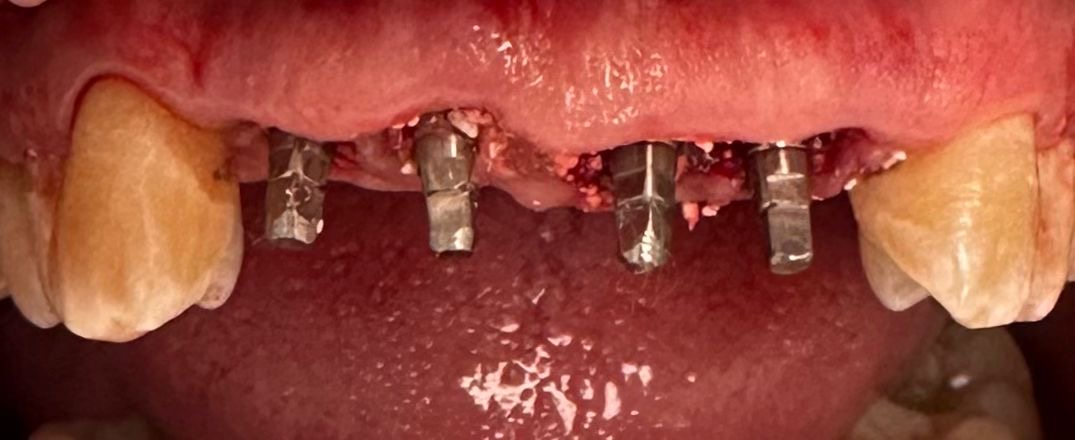

Realizamos la extracción de los cuatro incisivos superiores y, en el mismo acto quirúrgico, colocamos cuatro implantes de anclaje basal de 23 mm, buscando apoyo en el hueso cortical, el hueso más denso y estable. Además, se realizó una soldadura intraoral para rigidizar el conjunto y aportar máxima estabilidad desde el primer momento.

Para nuestro equipo clínico de la clínica dental Dr. Darío Castro – Dental Office esto supone la carga inmediata real.

«Dientes fijos desde el primer día».

Se colocó un provisional de larga duración para controlar la evolución de los tejidos y, como suele ocurrir en este tipo de casos, el paciente refirió molestias mínimas y una mejoría inmediata en función, estética y bienestar.